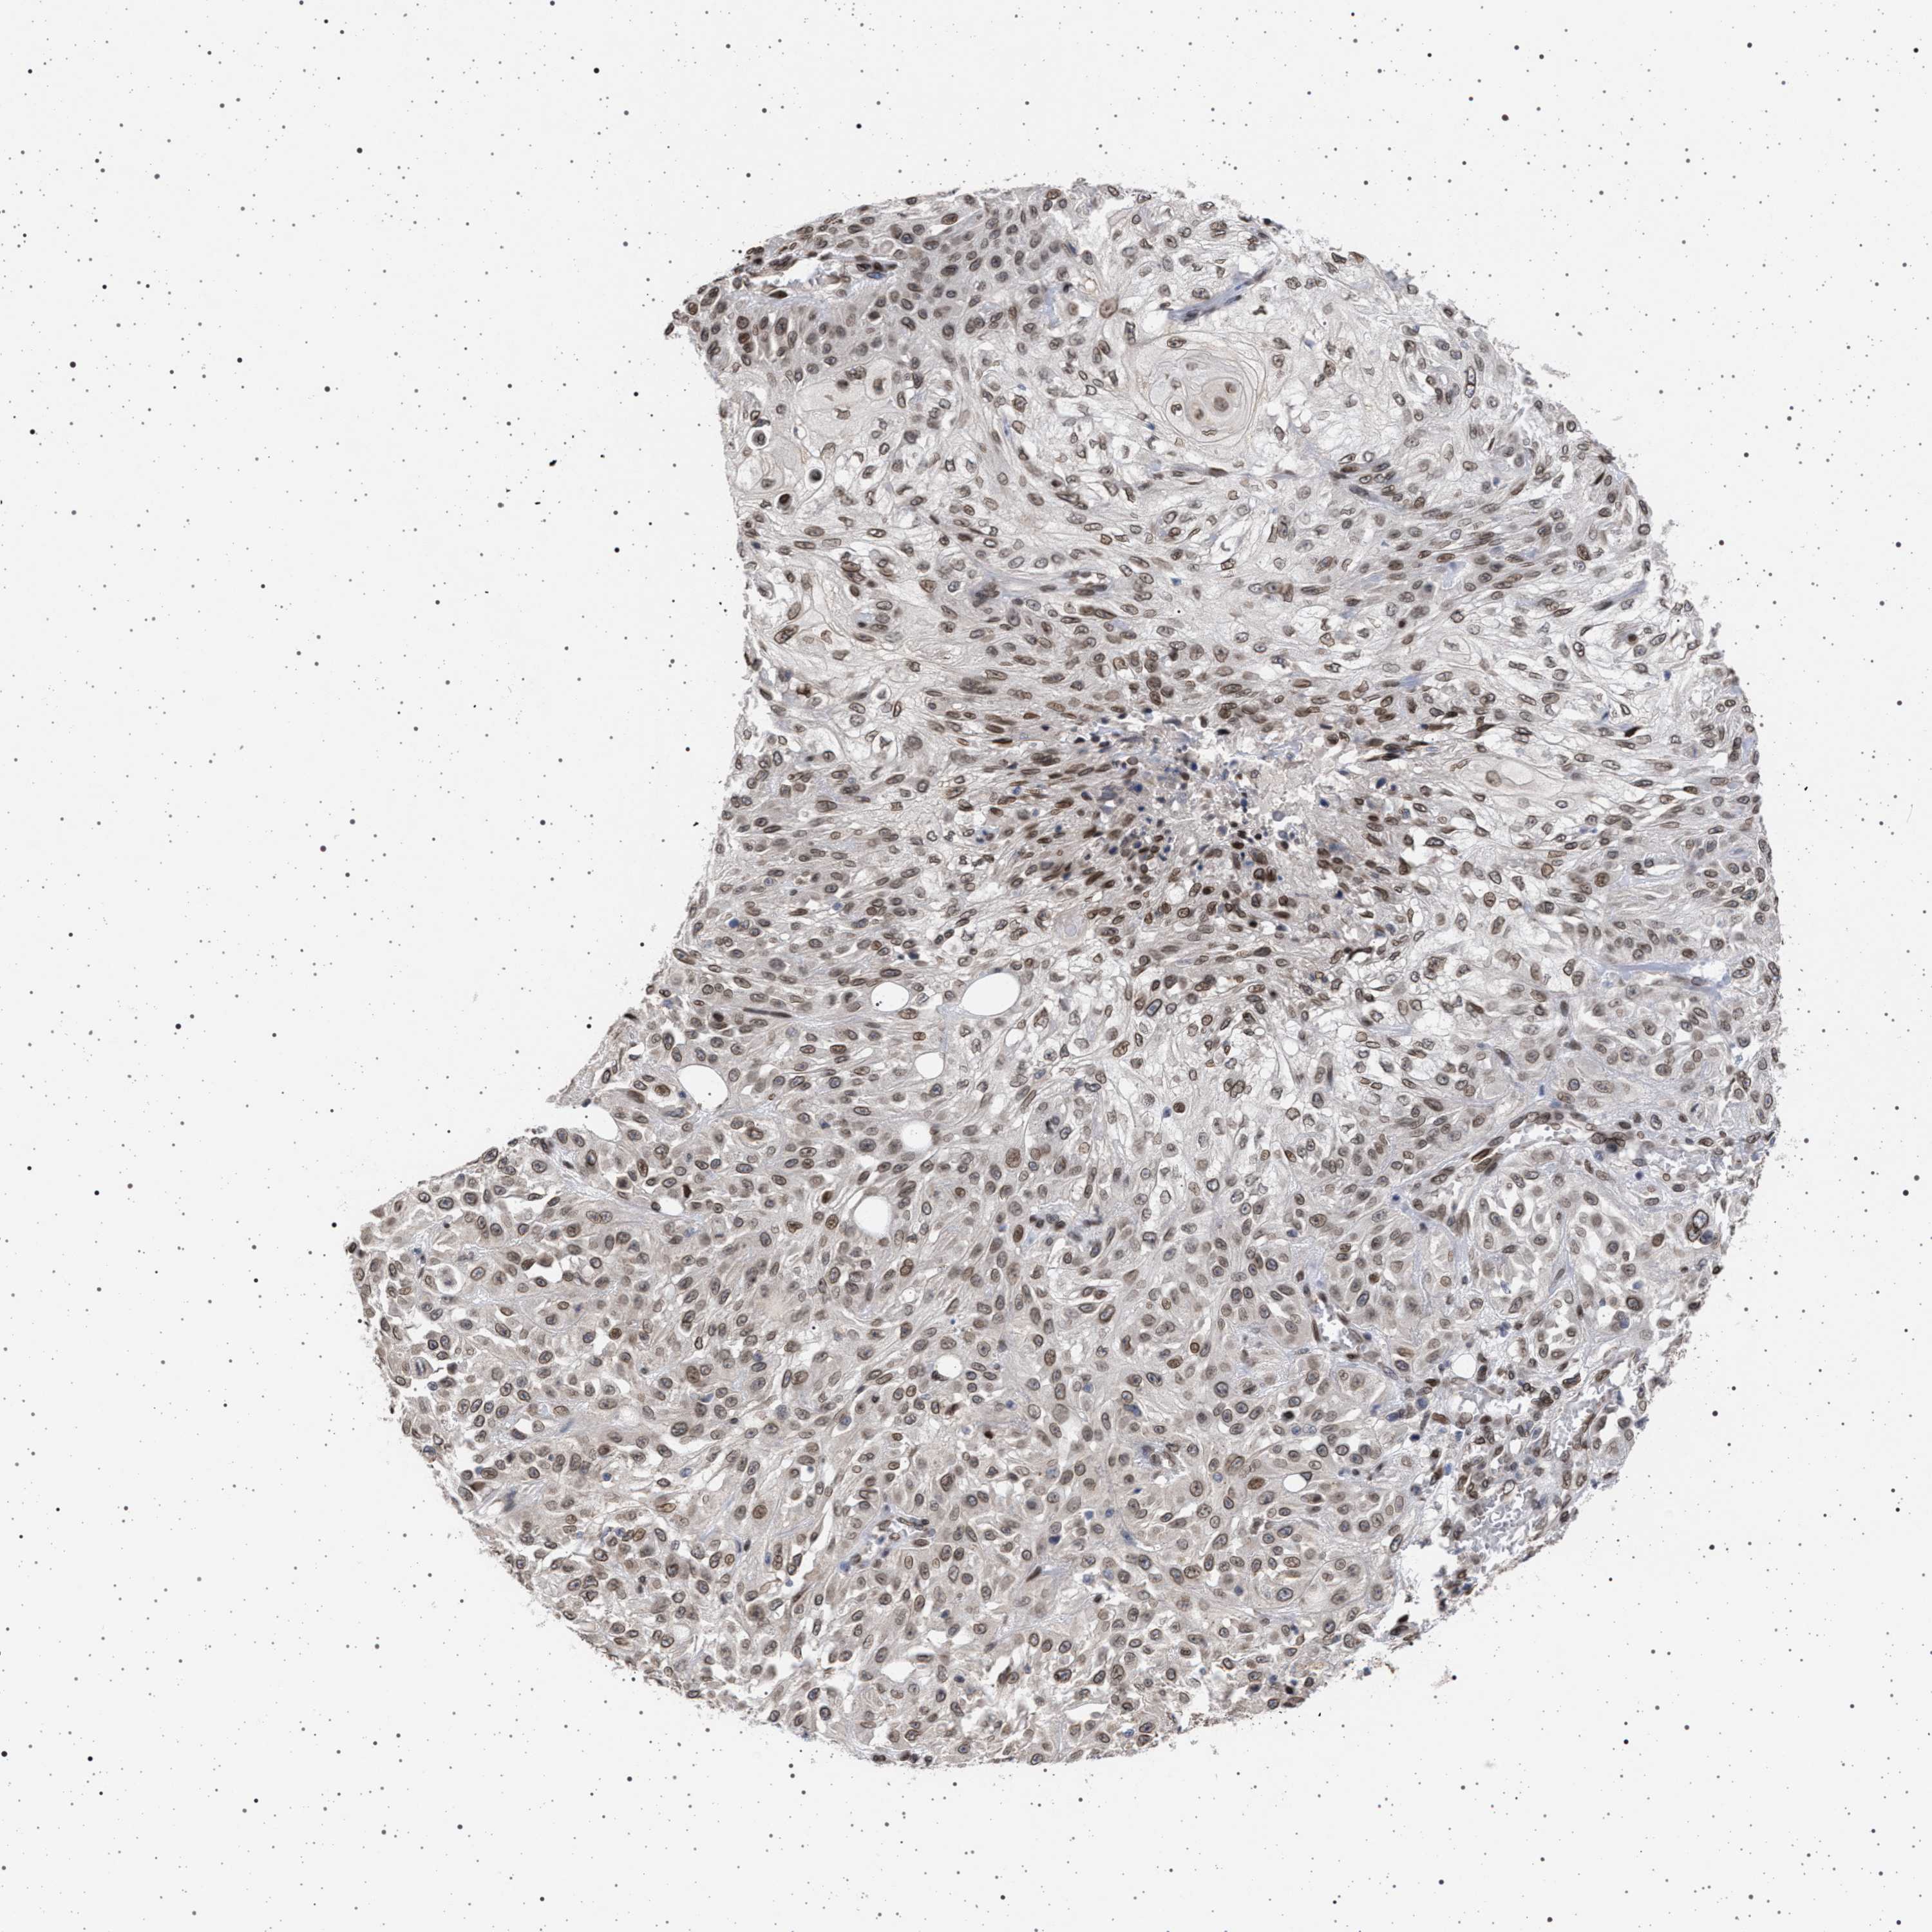

SKIN CANCER - Protein expressioni

A mouse-over function shows sample information and annotation data. Click on an image to view it in a full screen mode. Samples can be filtered based on level of antibody staining by selecting one or several of the following categories: high, medium, low and not detected. The assay and annotation is described here.

Each image is clickable and will lead to virtual microscopy that enables deeper exploration of all samples and also displays staining intensity scores, fraction scores and subcellular localization as well as patient and tissue information for each sample.

Antibody HPA021517

Staining

Medium

Intensity

Moderate

Quantity

75%-25%

Location

Cytoplasmic/membranous,nuclear

Squamous cell carcinoma, metastatic, NOS

Squamous cell carcinoma, NOS